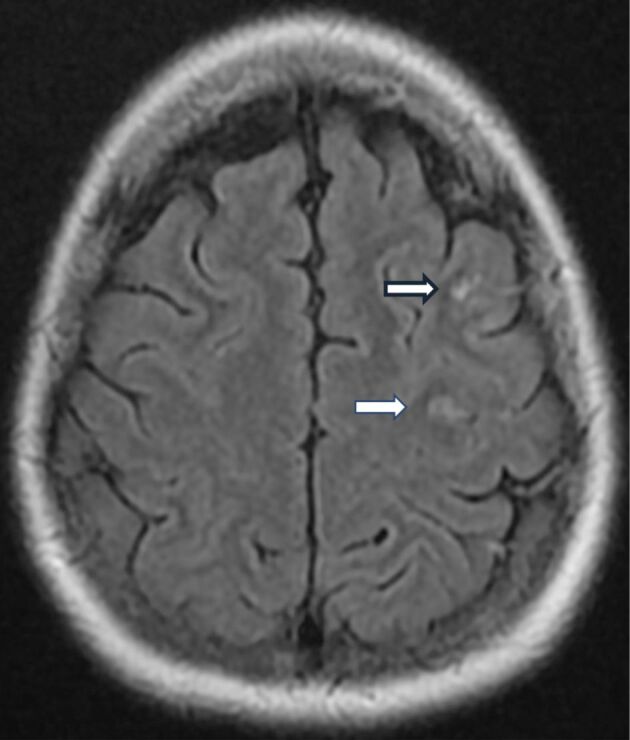

Cardiac myxoma (CM) is the most common benign tumor of the heart and an important etiology of stroke in young adults. The study aimed to provide the latest literature data on CMs and, in particular, on the association between CM and cardioembolic ischemic stroke. It also discussed a specific instance of atrial myxoma (AM) in a young patient who suffered an ischemic stroke linked with familial cavernomatosis. The case presentation focuses on a 43-year-old woman showed up at the hospital's Emergency Room for transient speech disorders lasting about 15 minutes. The physical examination revealed preserved mental and cognitive status. Cranial magnetic resonance imaging (MRI) showed three areas of microvascular ischemia (frontal, parietal, and left occipital), in addition to multiple cavernomatous lesions. Because these microvascular ischemias were located in different vascular territories, we considered the cause to be embolic and completed the investigation with a transesophageal cardiac ultrasound that revealed a mobile and heterogeneous tumor mass in the left atrium. Histopathological investigation with immunohistochemistry proved the tumor to be a CM. The patient therapy included a multidisciplinary approach, which led to surgical excision of the tumor. The co-existence of cerebral cavernous malformations (CCMs) and AM might thus be coincidental or induced by a common genetic component. More cases are needed to verify or disprove the concept of a shared genetic basis for CCMs and myxoma.